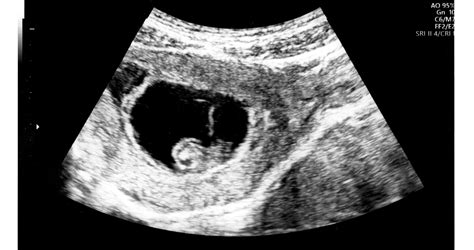

- Ultrahangvizsgálat: Már a 4-5. héttől látható a petezsák, a 6-7. héttől pedig már kimutatható a magzati szívműködés. Az első genetikai ultrahangvizsgálat a 12-14. hét között történik.